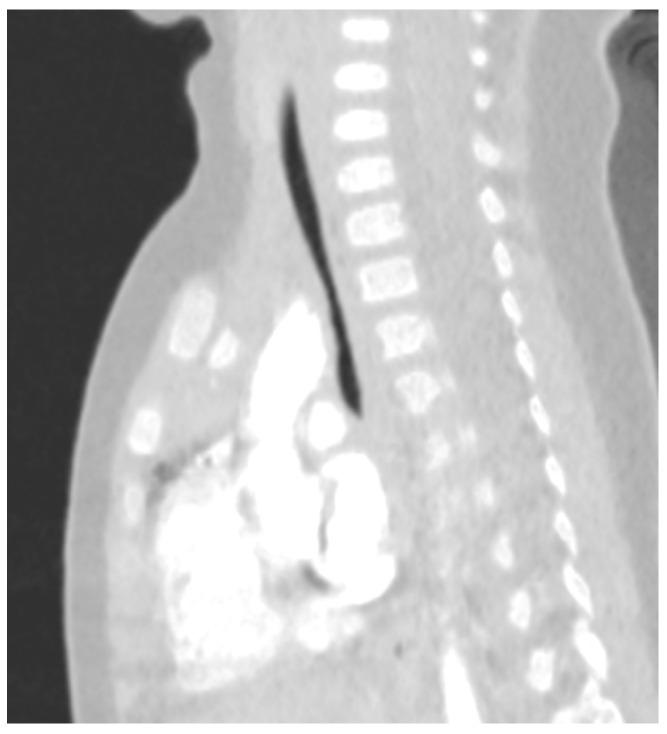

Down Syndrome (DS) is the most common chromosomal abnormality compatible with life. The life of patients suffering from DS can be strongly impacted by Recurrent Respiratory tract Infections (RRIs), leading to an increased rate of hospitalisation, a higher need for intensive care and fatality. With a literature review, we summarise here the main etiological factors for RRI in this category of patients, particularly focusing on airway malformations such as tracheomalacia, tracheal bronchus and bronchomalacia, comorbidities associated with the syndrome, like congenital heart diseases, dysphagia, gastroesophageal reflux, musculoskeletal involvement and obesity, and immunologic impairments, involving both innate and adaptive immunity. For these patients, a multidisciplinary approach is imperative as well as some preventive strategies, in particular vaccinations in accordance with their national schedule for immunization.

唐氏综合征(DS)是最常见的与生命相容的染色体异常疾病。患有唐氏综合征的患者的生活可能会受到反复呼吸道感染(RRIs)的严重影响,导致住院率增加、对重症监护的需求更高以及死亡率上升。通过文献综述,我们在此总结了这类患者反复呼吸道感染的主要病因,特别关注气道畸形,如气管软化、气管支气管和支气管软化,与该综合征相关的合并症,如先天性心脏病、吞咽困难、胃食管反流、肌肉骨骼受累和肥胖,以及涉及先天和适应性免疫的免疫缺陷。对于这些患者,多学科方法以及一些预防策略至关重要,特别是按照国家免疫计划进行疫苗接种。